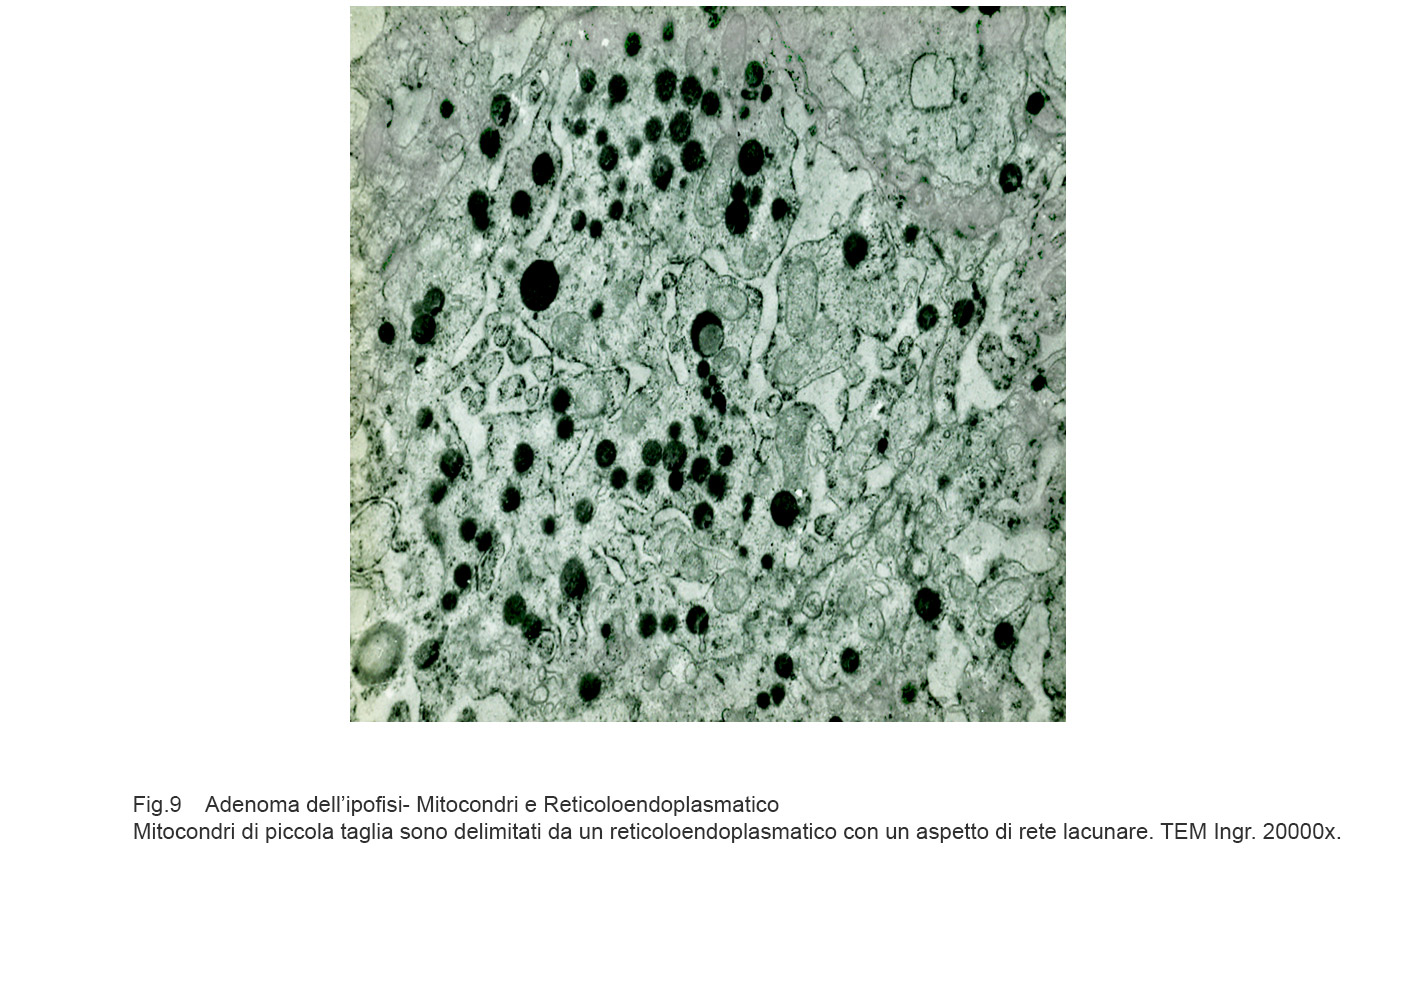

Mitocondri e R.E.: mitocondri rigonfi e privi di creste sono adiacenti ad ampia vacuolizzazione del reticolo endoplasmico; questi vacuoli sono frequentemente occupati da addensamenti di materiale amorfo e filamentoso(Reticoendoplasmatico in stato di stress).

Fig.7

Mitocondri e R.E. : mitocondri piccoli con una quota ridotta di creste sono incestellati da un reticolo endoplasmico che si snoda a rete con aspetto lacunare.(Reticoloendoplasmatico in stato di stress).

Fig.8